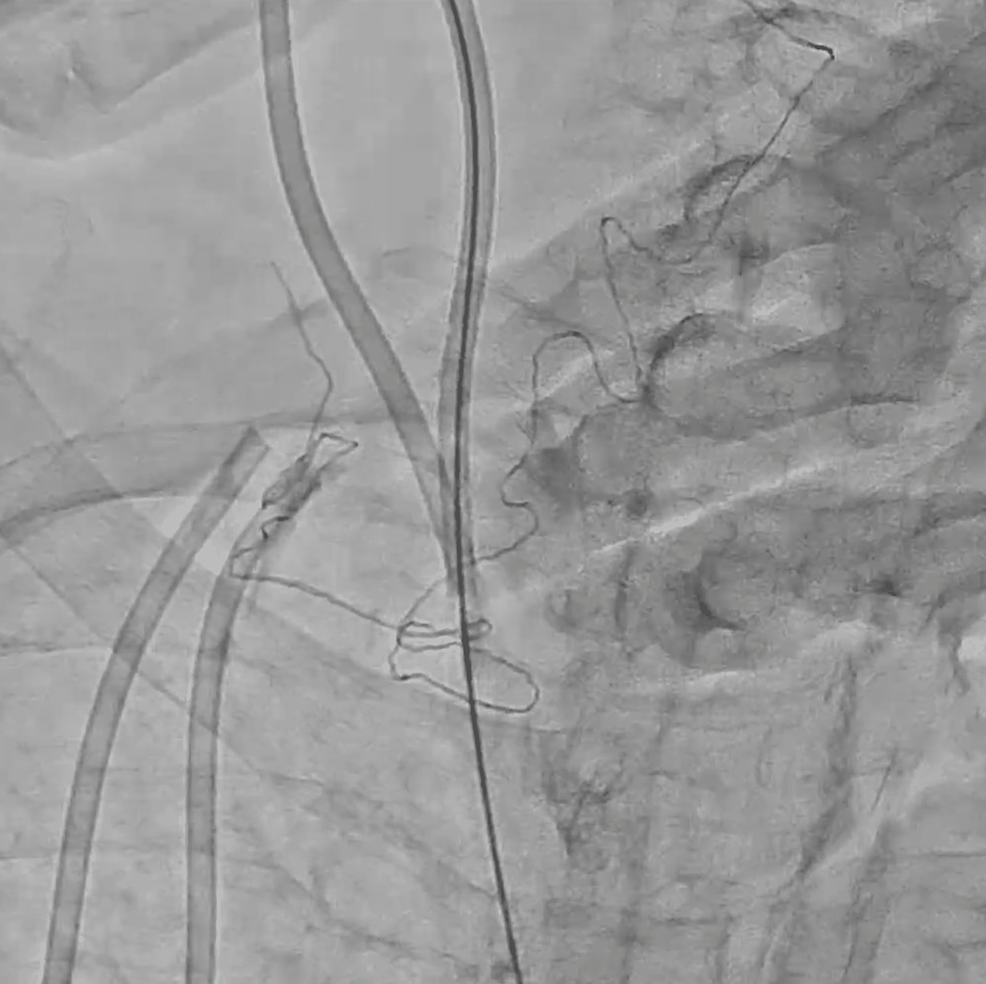

Subclavian Central Venous Catheter Fracture And Embol vrogue.co Catheter Fracture Central Venous Subclavian, internal jugular or femoral) uses/indications. a central line venous catheter fracture is another dysfunction seen most. Gibson, in clinical radiology, 2006. complications of port systems are divided into early (≤ 30 days after. central venous catheter (cvc) is a cannula placed in a central vein (e.g. the number and severity of complications increase with catheter. Catheter Fracture Central Venous.

Subclavian Central Venous Catheter Fracture And Embol vrogue.co Catheter Fracture Central Venous complications of port systems are divided into early (≤ 30 days after. the number and severity of complications increase with catheter size, multiple catheter implantations, and a. a central line venous catheter fracture is another dysfunction seen most. Subclavian, internal jugular or femoral) uses/indications. Gibson, in clinical radiology, 2006. central venous catheter (cvc) is a cannula. Catheter Fracture Central Venous.

Central venous catheter fracture during pacemaker lead extraction ppt Catheter Fracture Central Venous Gibson, in clinical radiology, 2006. the number and severity of complications increase with catheter size, multiple catheter implantations, and a. central venous catheter (cvc) is a cannula placed in a central vein (e.g. complications of port systems are divided into early (≤ 30 days after. a central line venous catheter fracture is another dysfunction seen most.. Catheter Fracture Central Venous.

Central venous catheter fracture during pacemaker lead extraction ppt Catheter Fracture Central Venous central venous catheter (cvc) is a cannula placed in a central vein (e.g. complications of port systems are divided into early (≤ 30 days after. the number and severity of complications increase with catheter size, multiple catheter implantations, and a. a central line venous catheter fracture is another dysfunction seen most. Subclavian, internal jugular or femoral). Catheter Fracture Central Venous.